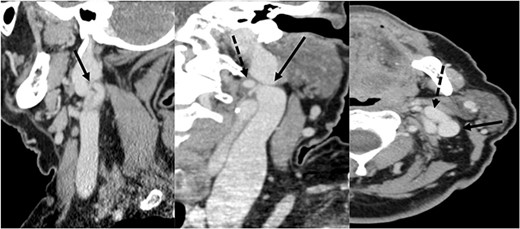

A 72-year-old woman underwent total laryngectomy + thyroid isthmectomy + bilateral (II–IV) laterocervical dissection for a G3 SCC of the right hemilarynx (involving the right true and false vocal cord and extending to the anterior commissure and left vocal cord). The preoperative radiology report did not mention any IJV variations. Nonetheless, a left IJV fenestration was observed in the preoperative study, raising the suspect of a possible SAN variant (Fig. 3). Pathological stadiation of the patient was pT4a (infiltration of thyroid cartilage and prethyroid soft tissue) pN2c, cM0. Intraoperatively, the fenestration of the left IJV, that was noticed during the CT, was confirmed. As for the first patient presented, the SAN nerve passed medially to the anterior vein and laterally to the posterior vein (Fig. 4).

SAN passes through medially to the anterior part (filled triangle) and laterally to the posterior part (star) of the fenestrated IJV (arrowhead); CCA: common carotid artery.